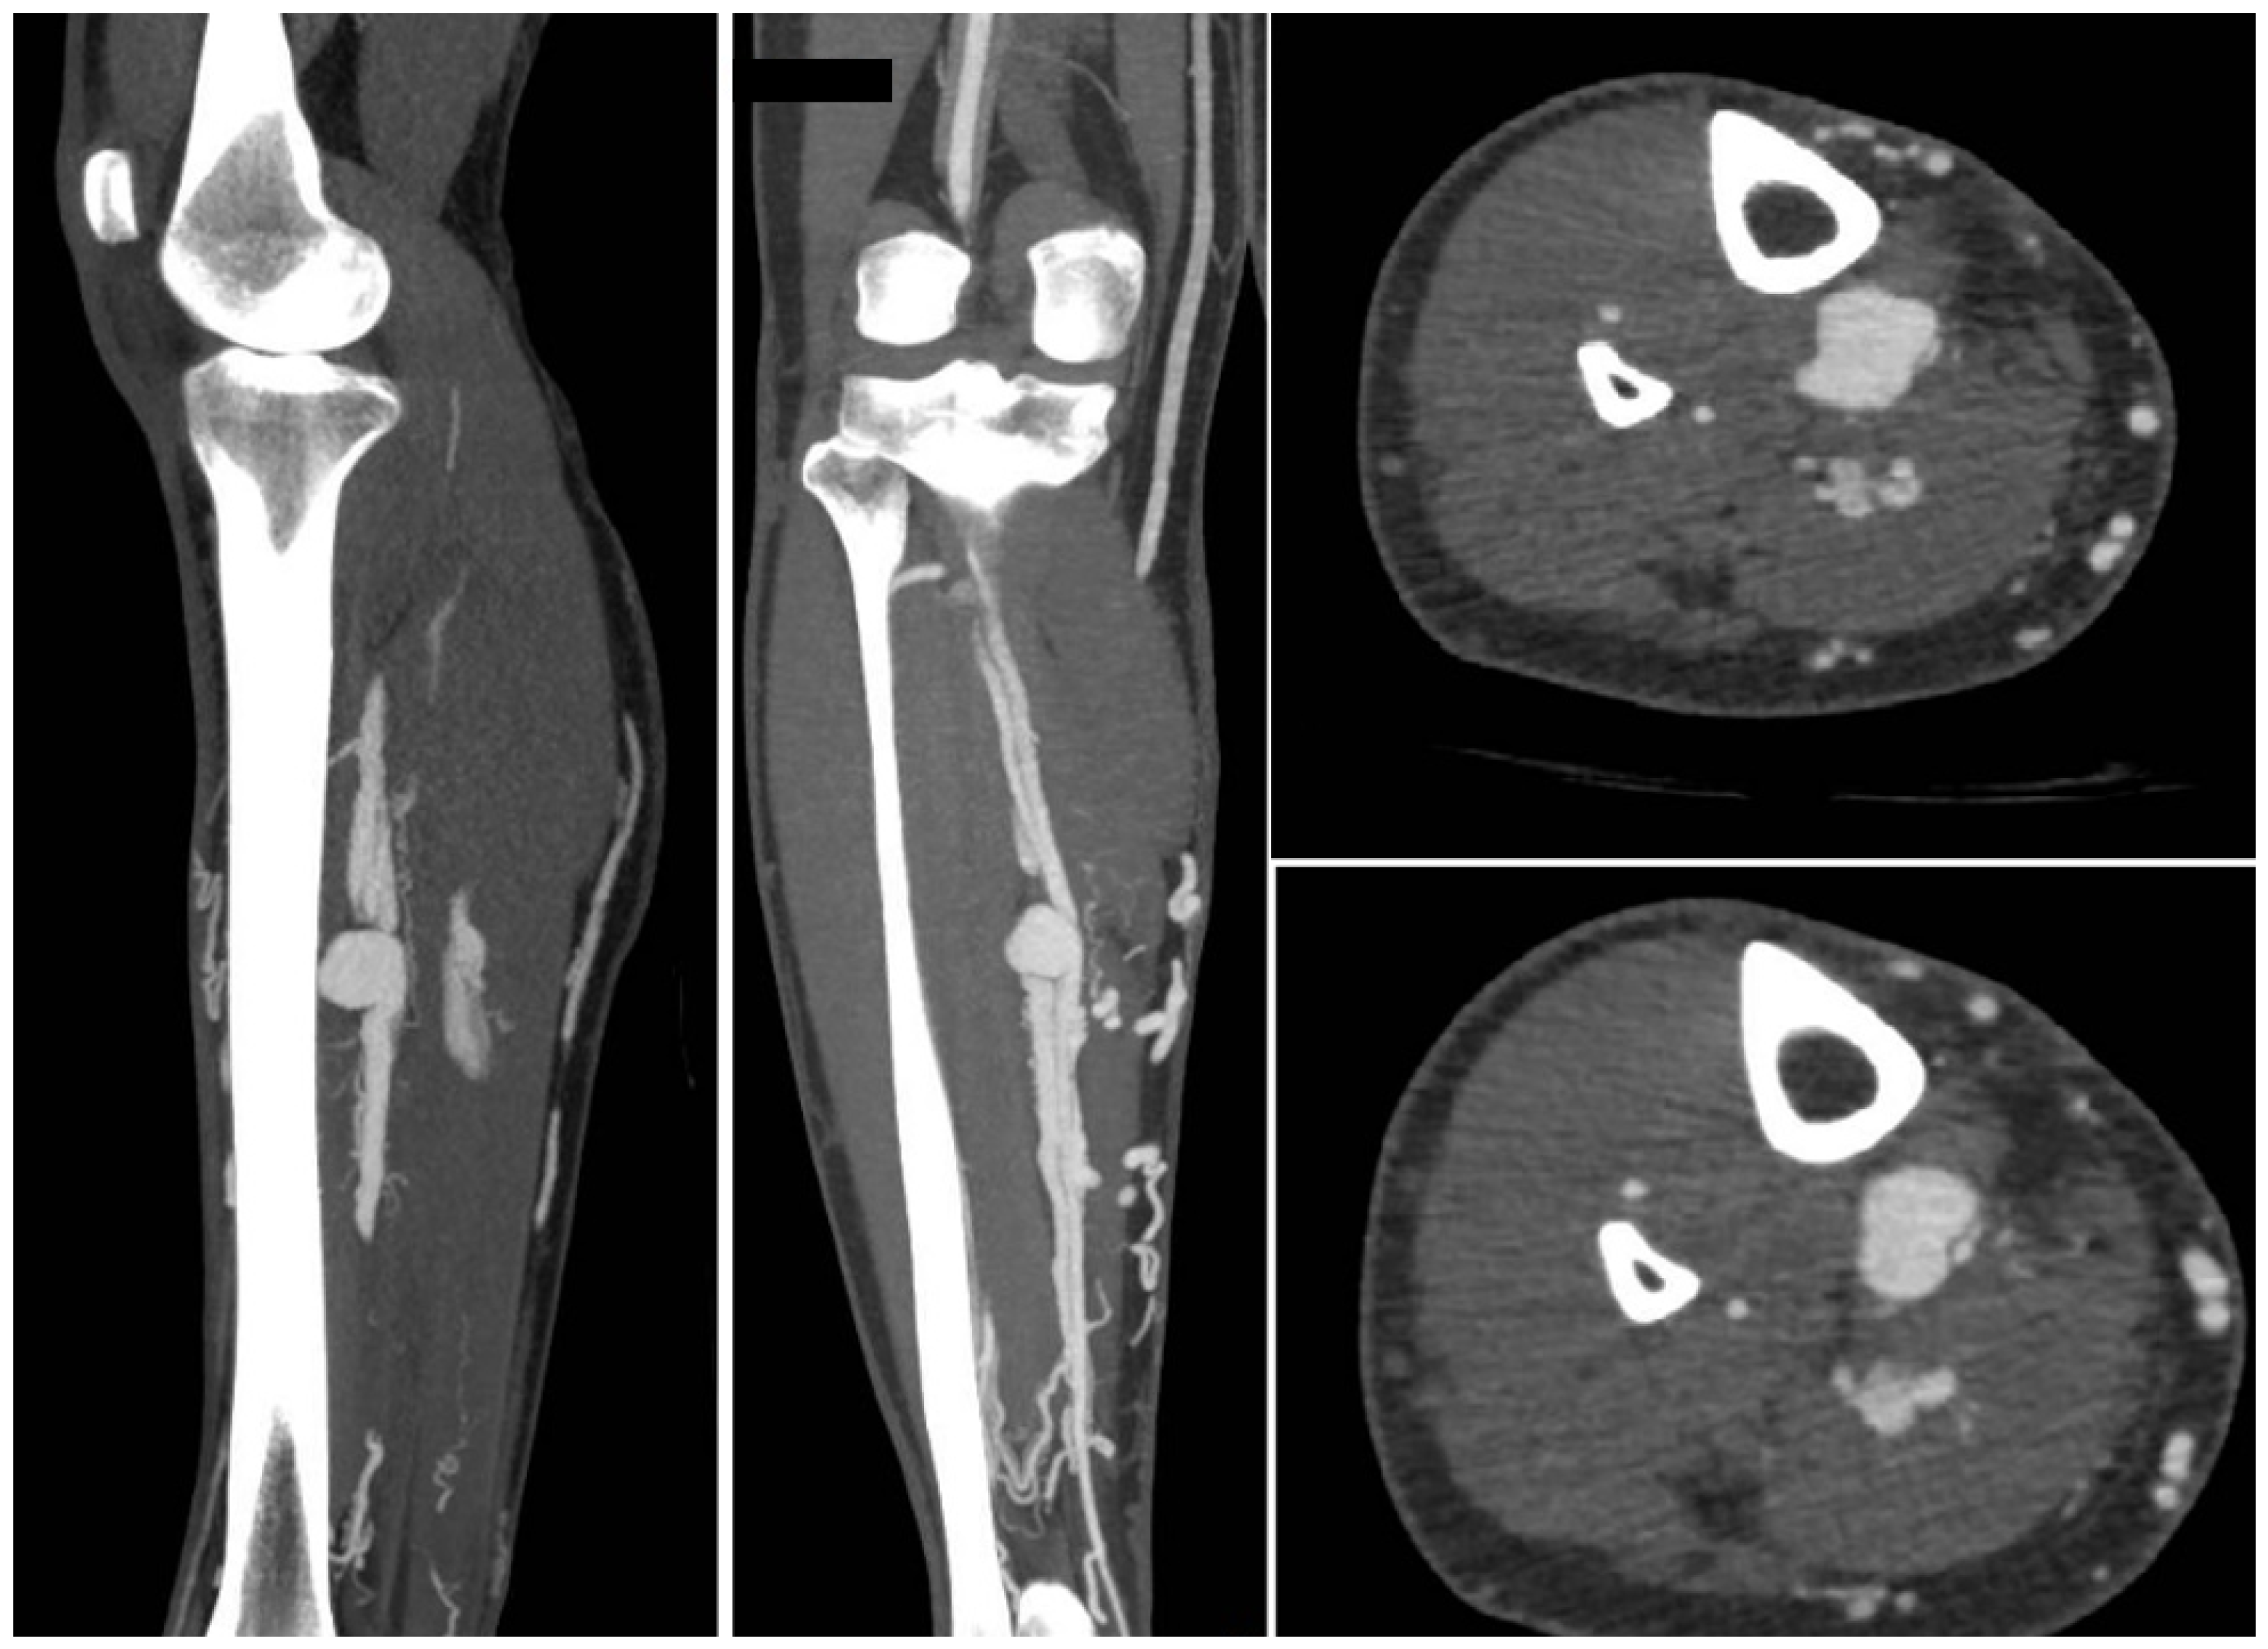

A 31-year-old man presented with calf pain in the right limb which had gradually increased in severity over the previous few months. The pain was throbbing in nature and was not associated with walking. There was a history of war injury to his lower leg in the region of the pain. The patient reported being hit by bomb shrapnel in the lower leg region. Physical examination revealed a pulsatile, tender mass in the mid-calf region. Duplex ultrasound revealed an aneurysm in the mid-calf region of the posterior tibial artery. To define the morphology of the aneurysm and the anatomy of the crural vessels, a CT angiogram was obtained. This confirmed the presence of an aneurysm of the PTA associated with an AV fistula to the deep posterior tibial veins (Figure 1).

Figure 1.

The CT angiogram shows the aneurysm of the posterior tibial artery with AV fistula (contrast uptake by the deep and the superficial veins).